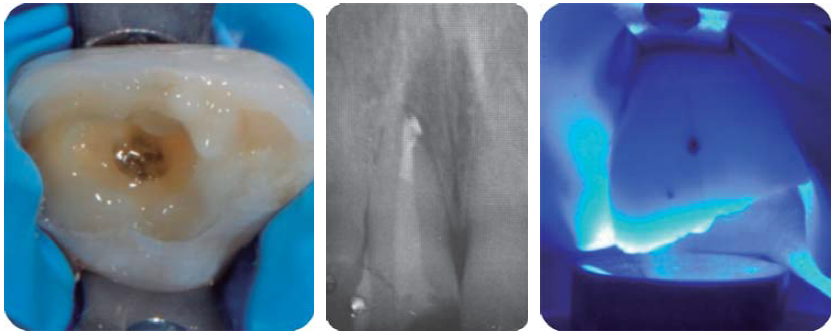

Paciente masculino de 21 años de edad, sano, presentando LDT al caer de una bicicleta; con fractura coronaria complicada de los dientes: 12, 11 y 21, con una evolución de 48 horas (Figura 1).

Debido a la evolución de dos días desde el accidente, el paciente presenta dolor e inflamación a la exploración extraoral, durante la exploración intraoral se observa la exposición pulpar de los dientes involucrados (Figura 2) e indica el tratamiento de urgencia a seguir, para disminuir el dolor e inflamación.

Consistió en el retiro de los fragmentos dentales (Figuras 3 a 6) (4,5) para tener una mejor visión del área y del posible tratamiento a ejecutar. Se realizó bajo anestesia local con lidocaína al 2% con epinefrina 1:100,000, luego se realizó la pulpectomía de los dientes 12, 11 y 21 dejando una medicación de hidróxido de calcio al 35% (UtraCal ® XS, pH 12.5, Ultradent) y como curación temporal un ionómero de vidrio (Figura 7).11,12

Paciente de sonrisa gingival que presenta fractura complicada de corona del diente 21 en el tercio medio coronal (Figura 3) y del diente 12 en el tercio cervical (Figura 4), fractura complicada de corona y raíz del diente 11 (Figura 5); gingivitis inducida por placa dentobacteriana (Figura 7), trasposición de los dientes 13 y 14, anodoncia verdadera de los dientes 15, 35 y 45, presentando los dientes temporales 55, 75 y 85.